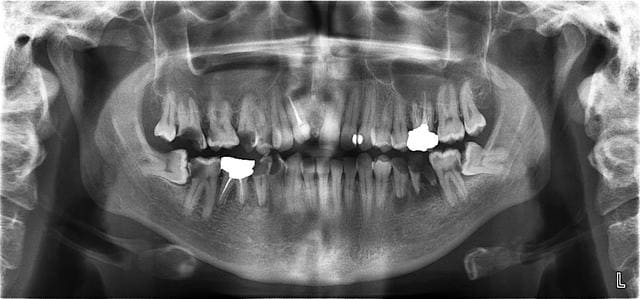

tiens j'ai un peu de temps petit cas similaire

petite évolution entre 2003 20006 2009

le problème reste quand même la brosse à dents mais elle est tellement gentille...

n'allez pas imaginer le top cela reste dans le style de la pano initiale pour le reste aussi

Autre question pour la 38 de la première pano. Il y a une superposition des racines avec le canal mandibulaire. Vous feriez un scan avant de la virer?

> Autre question pour la 38 de la première pano. Il y a une superposition des

> racines avec le canal mandibulaire. Vous feriez un scan avant de la virer?

non pas dans ce cas je ne fais de scan personellement qye lorsque les racines "plongent" dans le canal car la seule chose à redouter c'est qu'il soit "pris" entre les racines ce qui n'est pas ton cas